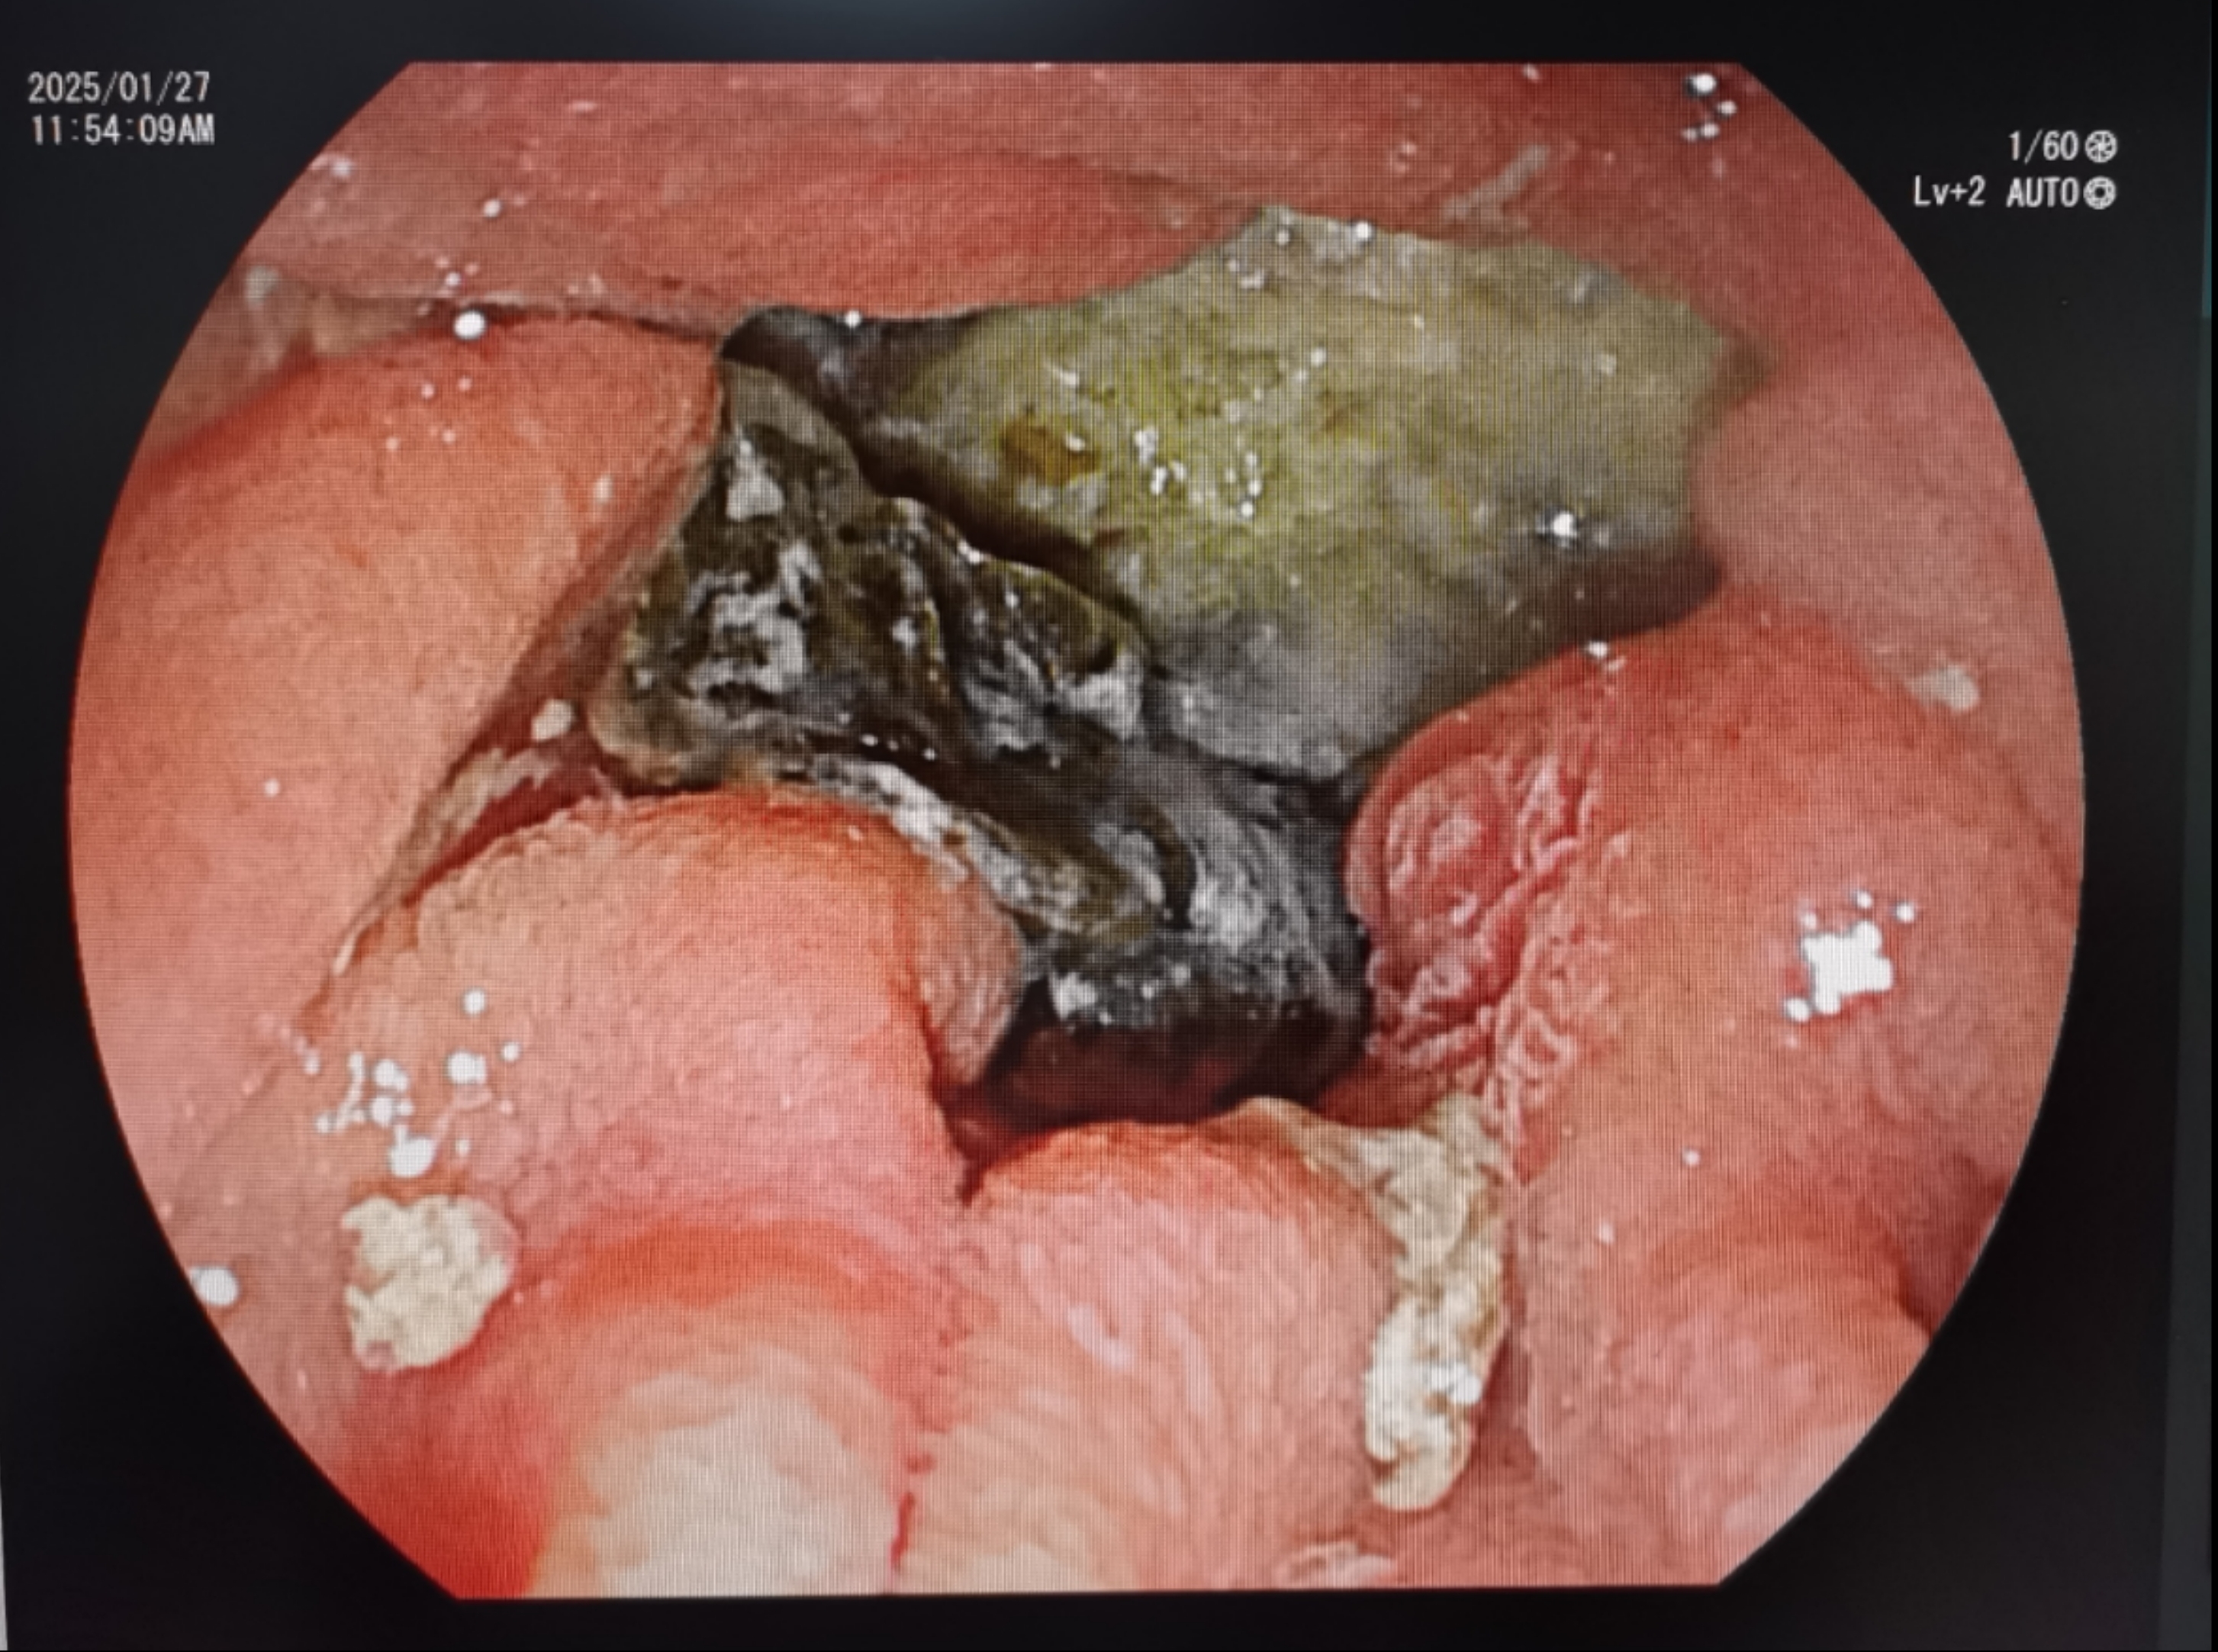

内镜下十二指肠乳头憩室内见食物残渣

术中挑战接踵而至:患者因疼痛无法采用常规俯卧位进行内镜下治疗,团队果断调整为左侧卧位操作。术中又发现患者十二指肠乳头开口位于憩室右侧壁,解剖结构异常导致插管难度倍增。闫秀娥最终以"毫米级"精细操作,成功完成胆管插管。考虑患者长期服用抗血小板药物,团队先行放置鼻胆管引流管,为患者解除胆道梗阻。术后患者转入消化内科病房继续治疗,待停药7天后再次行ERCP取石,最终顺利取出胆管结石。